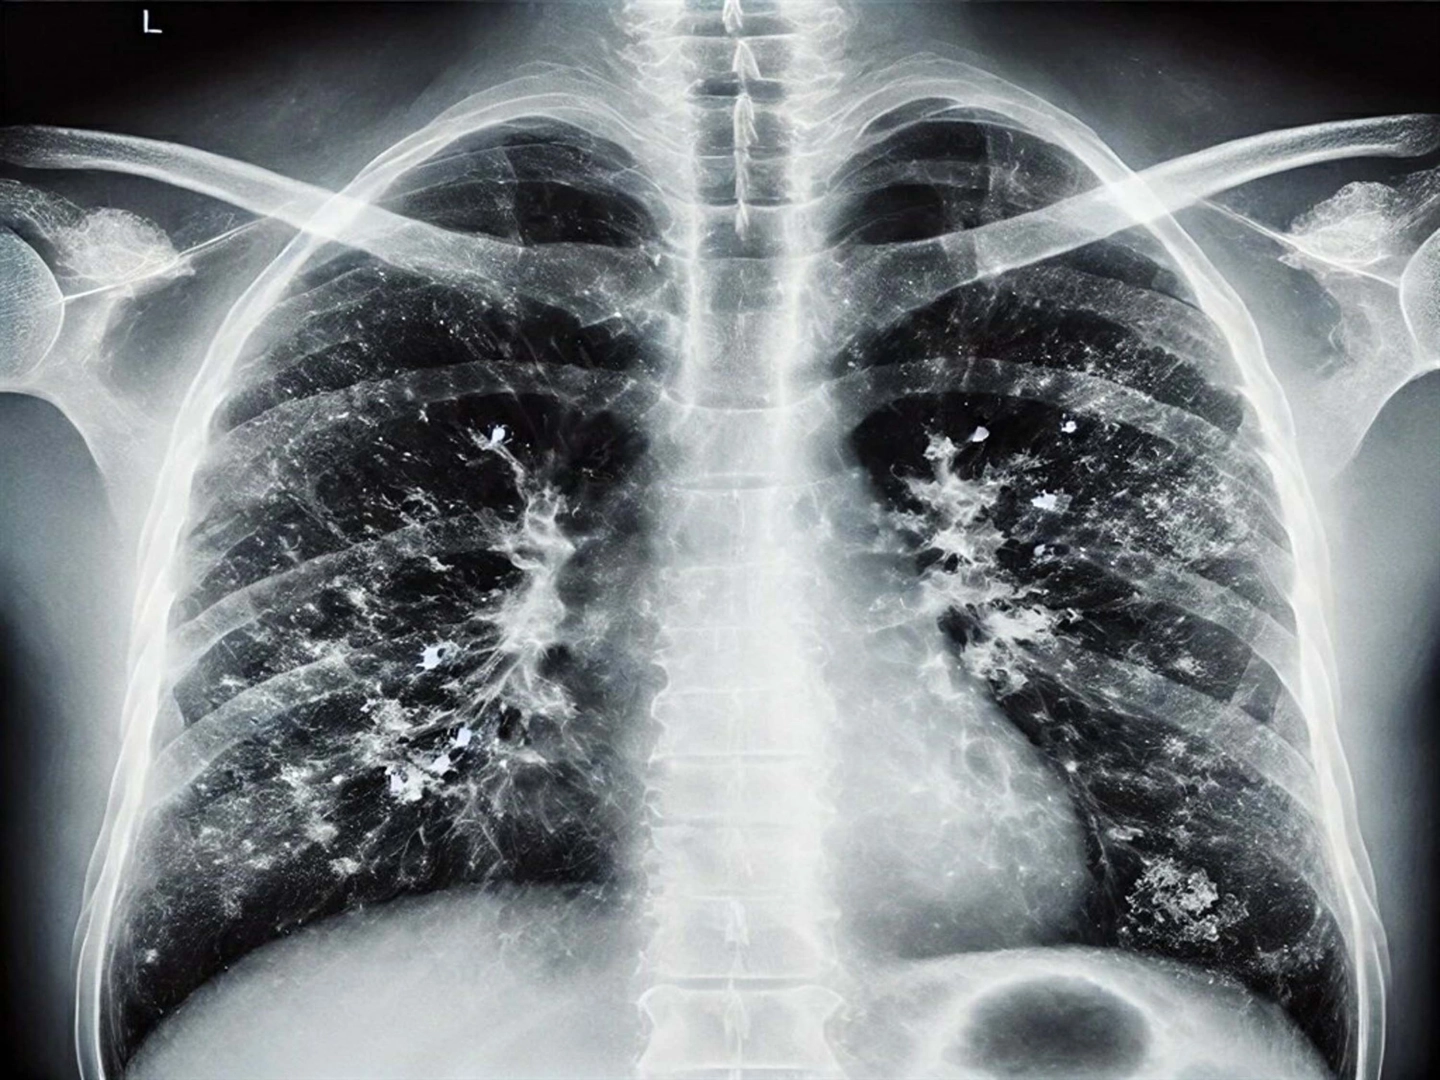

İl Sağlık Müdürlüğü Halk Sağlığı Hizmetleri Başkanlığı Başkan Yardımcısı Doktor Metin Kızılelma, kış aylarında havanın soğumasıyla, solunum yolu enfeksiyonlarında bir miktar artış beklendiğini ve bu durumun doğal olduğunu belirterek, enfeksiyona karşı önlemleri anlattı. Doktor Kızılelma, açıklamasında "Özellikle hasta olan kişinin kapalı ortamlarda maske kullanması viral enfeksiyonların yayılmasını bir miktar engelleyecektir. Yine kalabalık yerlere gireceksek hasta olmayan kişiler de maske kullanabilir. En önemli unsurlardan biri de kişisel hijyen. Burada da en çok üzerinde durduğumuz konu el yıkamadır. Bu el yıkama, sadece suyla el yıkamak değil, sabunla ve suyla, en az 20 saniye boyunca ellerimizi ovuşturarak yıkamaktır. Ellerimizi yıkadıktan sonra da kurulamalıyız" dedi.

Solunum yolu enfeksiyonu etkenlerinin birden fazla olduğunu söyleyen doktor Kızılelma, "Bu etkene göre geçirdiğiniz solunum yolu enfeksiyonunun ağırlığı da değişebilir. O yüzden kişinin solunum yolu enfeksiyonu geçirirken bol sıvı alması ve dinlenmesi çok önemli. Ateş yüksekliği, öksürük olması, kendini kötü hissetmesi durumunda hasta mutlaka bir hekim tarafından muayene edilmeli" dedi. (DHA)